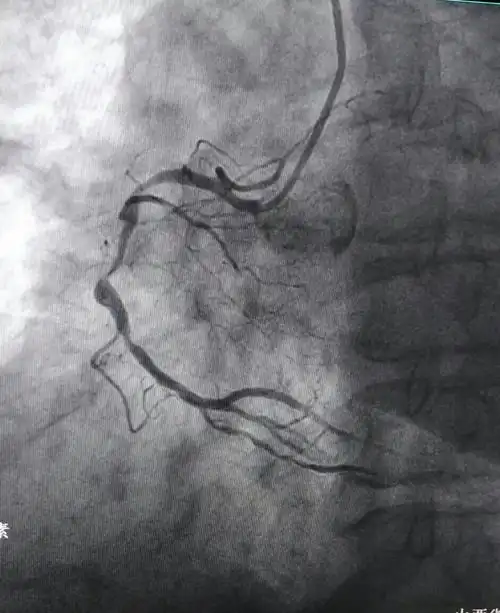

前降支植入一枚支架后影像资料